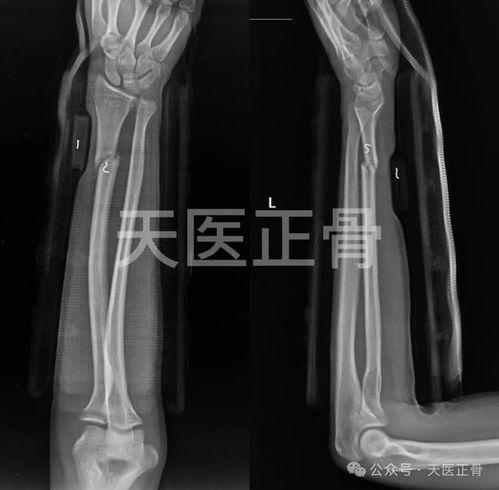

2. 胫腓骨骨折:胫腓骨骨折多发生在踝关节扭伤或跌倒时。